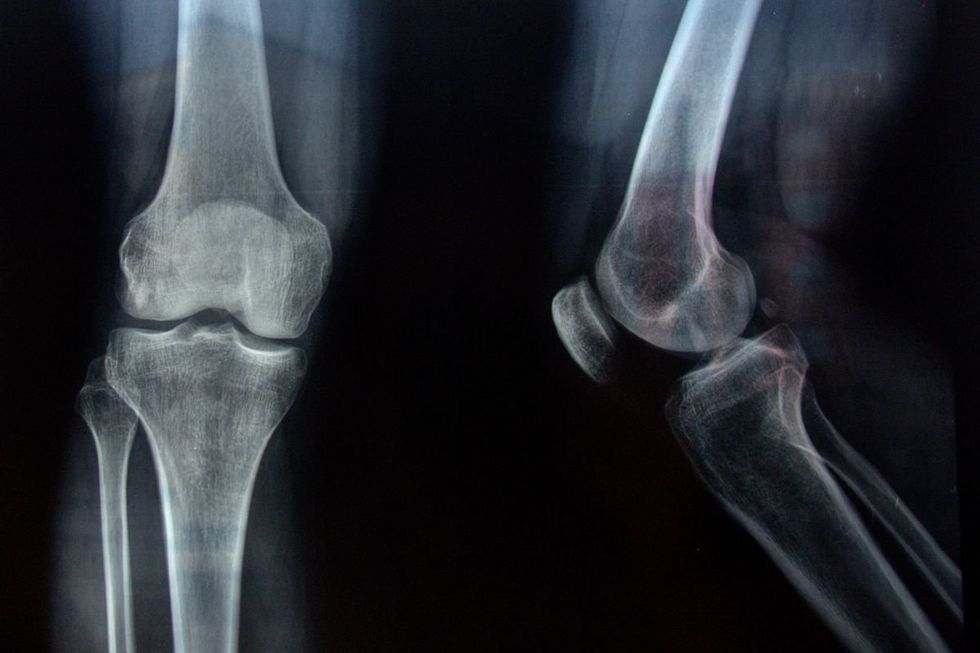

The time you eat matters more than you might think for bone health

|GETTY

When it comes to protecting your bones, what time you eat matters more than you might think.

Sticking to a consistent eating pattern helps bones carry out their repair cycle